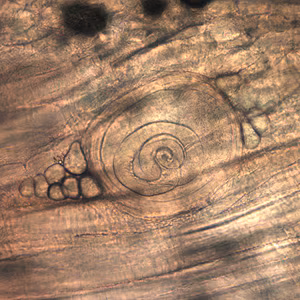

Larvae of Trichinella from bear meat.